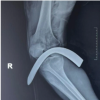

At her 2-week post-operative visit, she was transitioned into a short leg cast and remained non-weight-bearing. At her 6-week post-operative visit, the patient was transitioned to a CAM boot. to allow for ankle range of motion. She remained non-weight-bearing and began physical therapy. At 10 weeks postoperatively, the patient progressed to weight-bearing as tolerated and continued physical therapy. By her 6-month visit, the patient returned to full weight-bearing without post-operative complications. Radiographs showed maintenance of ankle alignment with no radiographic or clinical signs of instability (Fig. 4).